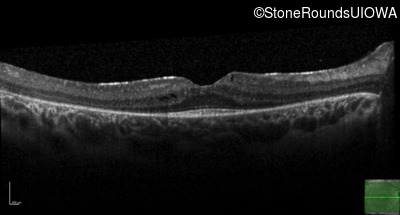

Age at visit: 7 years

This 7 year old girl has had very poor vision in dim light and slightly subnormal acuity her entire life.